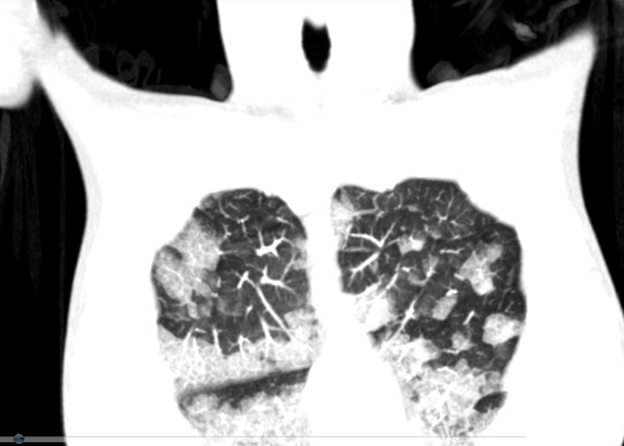

圖一、胸部X光片。左圖,之前就醫的X光片,肺部無明顯異常 ,雙側乳房手術植入假體(箭頭)。

右圖,此次就診的X光片,雙下肺部呈現明顯浸潤,雙側肋膜角度(CP angle)仍清楚可見銳角。